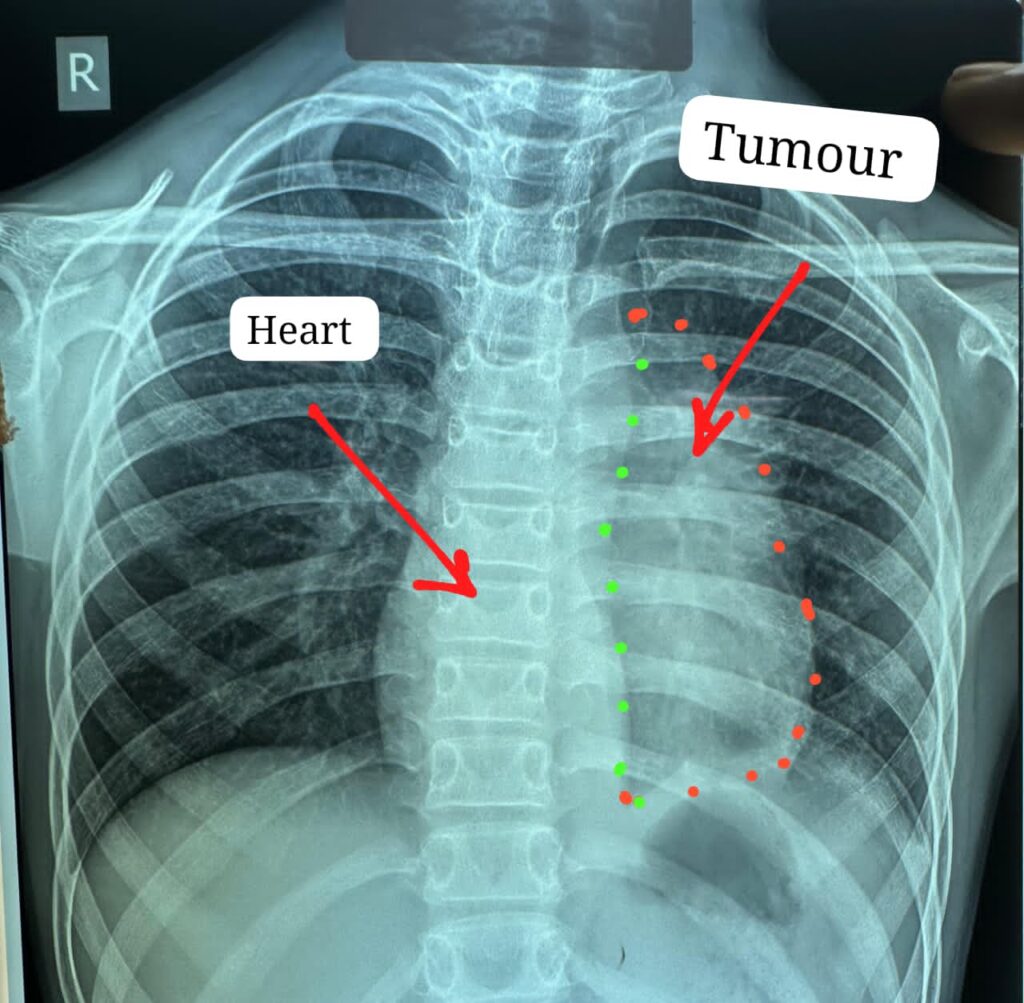

अस्पताल के हार्ट, चेस्ट एवं वैस्कुलर सर्जरी विभागाध्यक्ष डॉ. कृष्णकांत साहू और उनकी विशेषज्ञ टीम ने इस जटिल सर्जरी को अंजाम दिया। डॉक्टरों के अनुसार यह ट्यूमर सामान्यतः 40 से 60 वर्ष की आयु के लोगों में पाया जाता है और बच्चों में इसका होना अत्यंत दुर्लभ है। इस मरीज के मामले में ट्यूमर ने हृदय के साथ-साथ पेरिकार्डियम (दिल की झिल्ली), फ्रेनिक नर्व, महाधमनी (एओर्टा), मुख्य पल्मोनरी आर्टरी (एमपीए), लेफ्ट एट्रियम और फेफड़ों को भी अपनी चपेट में ले रखा था, जिससे ऑपरेशन की जटिलता कई गुना बढ़ गई थी। ऐसे मामलों में ट्यूमर को पूरी तरह निकाल पाना, जिसे आर-0 रिसेक्शन कहा जाता है, लगभग असंभव माना जाता है, लेकिन अस्पताल में उपलब्ध आधुनिक तकनीक और हार्ट-लंग मशीन की सहायता से यह चुनौतीपूर्ण कार्य सफलतापूर्वक किया गया।

ट्यूमर का आकार बड़ा और कई महत्वपूर्ण अंगों से चिपका होने के कारण सर्जरी के लिए ड्यूल एप्रोच तकनीक अपनाई गई, जिसके तहत मरीज के स्टर्नम और पसलियों दोनों स्थानों पर चीरा लगाया गया, जिसे मेडिकल भाषा में स्टर्नोटॉमी और थोरेक्टोमी कहा जाता है। लगभग चार घंटे तक चली इस सर्जरी के दौरान मुख्य ट्यूमर के साथ-साथ फेफड़ों की प्लूरल कैविटी में फैले तीन अन्य सैटेलाइट ट्यूमर को भी सावधानीपूर्वक निकाल दिया गया, ताकि भविष्य में कैंसर के दोबारा फैलने की संभावना को कम किया जा सके। निकाले गए ट्यूमर का आकार लगभग 12×8 सेंटीमीटर और वजन करीब 400 ग्राम था। ऑपरेशन के दौरान मरीज की स्थिति को स्थिर बनाए रखने के लिए हार्ट-लंग मशीन तैयार रखी गई थी और आवश्यकता पड़ने पर चार यूनिट रक्त भी चढ़ाया गया। इस प्रक्रिया में हार्ट की झिल्ली, फ्रेनिक नर्व तथा फेफड़े के कुछ हिस्सों को भी निकालना पड़ा, साथ ही ट्यूमर के लेफ्ट एट्रियम से चिपके होने के कारण हृदय के इस हिस्से की मरम्मत भी की गई।